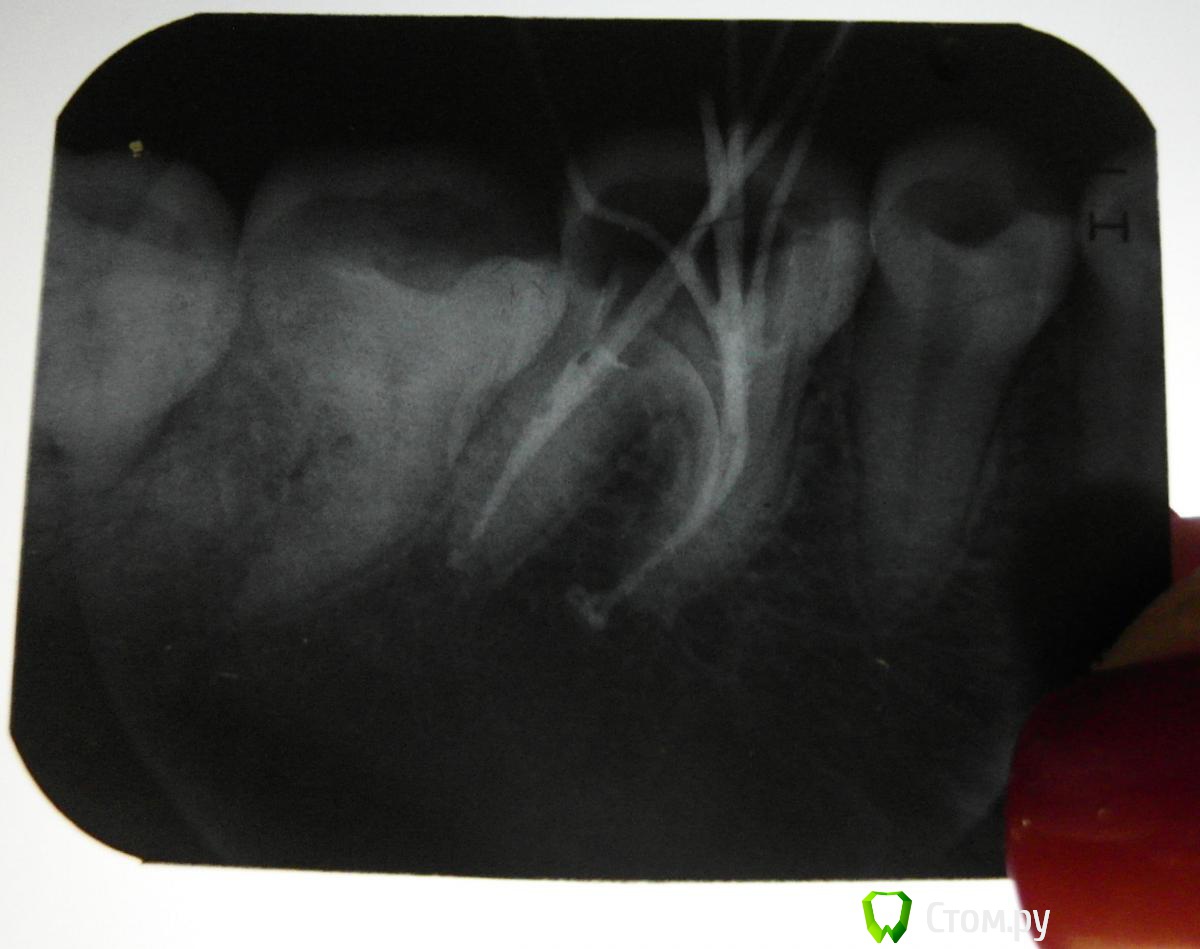

MariaMi Опубликовано 31 января, 2014 Поделиться Опубликовано 31 января, 2014 (изменено) Здравствуйте, уважаемые посетители форума.Хочу спросить совета.Накануне предстоит установка брекетов. До этого решила зубы пролечить. На 36 зубе была пломба, которая уже наполовину отвалилась. Зуб не болел, никак не беспокоил (кроме того, что внешне выглядел полуразрушенным).При лечении оказалось, что нужно пломбировать каналы.Снимок во время пломбирования каналов во вложении. На данный момент стоит временная пломба. Вопросы: 1. Как можно оценить проведенное пломбирование по этому снимку?2. Как может отразиться состояние этого зуба на установке брекет-системы (если ответ на данный вопрос в рамках данного раздела не возможен, прошу оставить без внимания).3. Какова вероятность того, что может быть осложнение и придется каналы перелечивать. Какие негативные последствия некачественного пломбирования каналов возможны, какова вероятность. (Данный вопрос назрел по причине, что на мой взгляд несведущего в стоматологии человека, пломбирование выполнено не идеально....)Точнее, есть ли вероятность того, что этот зуб не побеспокоит в будущем? Очень переживаю, перерыла весь интернет (кажется, с этого момента я уже весьма сведуща). Надеюсь, получить успокоение... Ну или пинок к активным действиям. Благодарю за ответы! Изменено 31 января, 2014 пользователем MariaMi Ссылка на комментарий

DmitrySH Опубликовано 31 января, 2014 Поделиться Опубликовано 31 января, 2014 Не катастрофа, но лучше перелечить. 1. Каналы запломбированы почти одной пастойНет плотной пломбировки каналов ( 2 штифта в одном канале, это не серьезно) Во время лечения зуб не изолировали коффердамом. ( да даже если все было чисто, то во время снимка слюна уж точно попала в полость) 2. Если щечная стенка цела. то никак. Если зуб разрушен, то нужно восстановить, чтоб было к чему приклеить брекеты. 3. Есть вероятность и того и другого Ссылка на комментарий